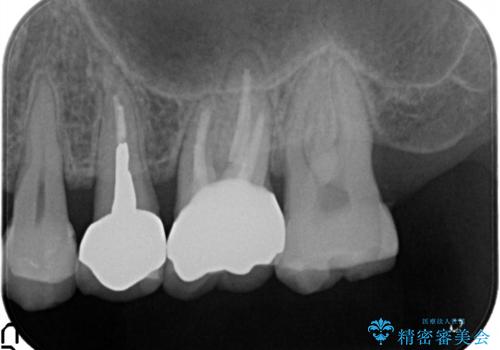

- 以前から奥歯に違和感があることを主訴に来院されました。歯肉にサイナストラクトを認めたため、再根管治療を行った後オールセラミッククラウンにて修復治療を行いました。根管治療は林先生に依頼しております。

- 13万円(根管治療別途)費用は治療当時の料金となります